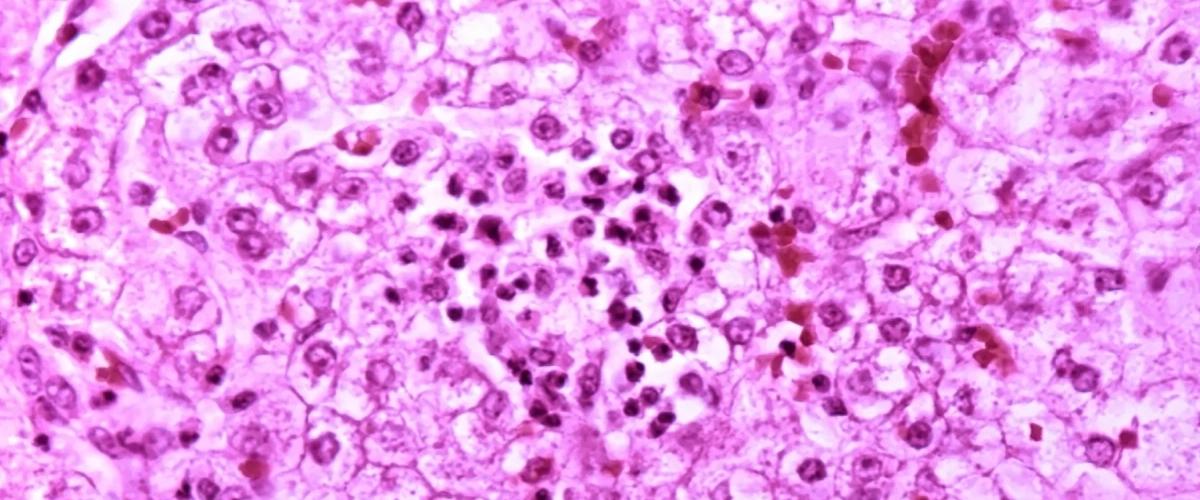

Ученые из Университета Индианы обнаружили в цикле мочевины — ключевом процессе преобразования аммиака в организме — причину развития жировой болезни печени. По статистике, этот диагноз считается наиболее распространенным заболеванием печени у взрослых и детей. У пациентов в течение многих лет может происходить избыточное накопление жира в ткани печени, после чего хроническое воспаление приводит к развитию фиброза, а на последних стадиях развивается цирроз и рак печени.

Теперь ученые установили, что нарушения в цикле мочевины приводят к поломкам в цикле трикарбоновых кислот — ключевом сигнальному пути энергического обмена. В результате эти процессы способствуют неэффективному использованию калорий, избыточному накоплению жира и, в конечном итоге, воспалению и фиброзу.